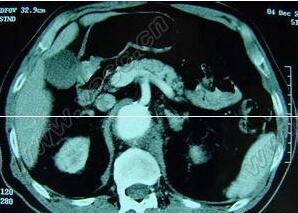

主动脉窦动脉瘤破裂主动脉窦动脉瘤破裂根据病史、心杂音的性质和传导方向。结合心电图、X线检查和超声心动图可作出诊断。需鉴别诊断的是动脉导管未闭、高位室间隔缺损伴主动脉瓣关闭不全、冠状动脉瘘、左冠状动脉起源于肺动脉等。仔细分析体征结合超声心动图不难鉴别。逆行性升主动脉造影的特征为右冠状或无冠状动脉窦扩大畸形,右心室流出道和肺动脉 或右心房早期显影,可资鉴别。